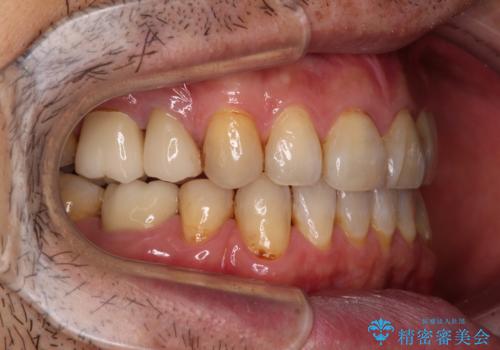

- むし歯による奥歯の痛みを気にして来院された患者様です。

神経にまでむし歯の及んでいる歯や、既に根管治療がされている歯に痛みがあったため、まずは根管治療を行うこととしました。

その後、以前行った抜歯矯正の後戻りをインビザライン・ライトにより改善し、むし歯や銀歯はオールセラミッククラウンにて補綴治療することとしました。

痛みは速やかに引き、銀歯や黒く変色したむし歯がセラミッククラウンで自然な色合いに仕上がり、患者様には大変満足していただきました。